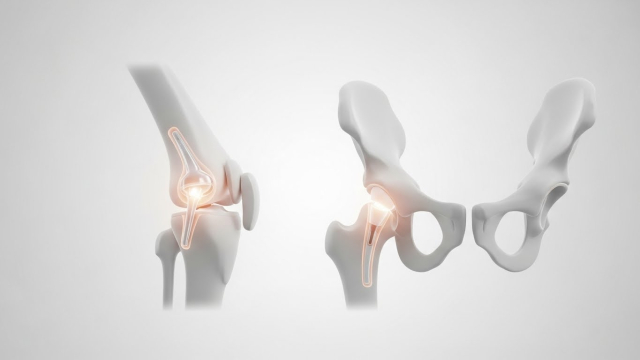

2) 무릎 vs 고관절, 비용 차이 포인트

같은 “인공관절”이라도 부위와 수술 난이도, 입원/재활 패턴이 달라서 총비용이 달라집니다. 특히 고관절은 골절/괴사 등 상황에 따라 입원·재활이 달라질 수 있어요.

• 무릎: 통증·변형·보행 문제 중심

• 고관절: 고관절 통증 + 절뚝거림/가동범위 제한, 골절 이슈까지

상세 3) 무릎·고관절별로 비용이 달라지는 이유

무릎은 보행·계단·앉았다 일어날 때 통증이 심해 수술을 고민하는 경우가 많고, 고관절은 통증 위치가 사타구니/엉덩이 쪽으로 나타나 “허리 문제”로 착각하기도 합니다. 부위마다 수술 접근 방식과 회복 루틴이 달라져 비용 구조도 달라질 수 있어요.

• 무릎: 수술 후 초기 보행·근력 회복 중심 재활이 중요

• 고관절: 자세·보행 교정 + 낙상 위험 관리가 함께 중요